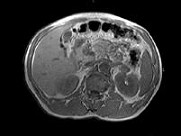

- 单项选择题男,52岁, 下肢无力伴多饮多尿2年余,实验室检查: 低血钾,血醛固酮水平及24h尿醛固酮定量超过正常值, MRI检查如图所示,应诊断为 ( )

A、左肾上腺囊肿

B、左肾上腺腺瘤

C、左肾上腺嗜铬细胞瘤

D、左肾上腺髓脂瘤

E、左肾上腺转移癌